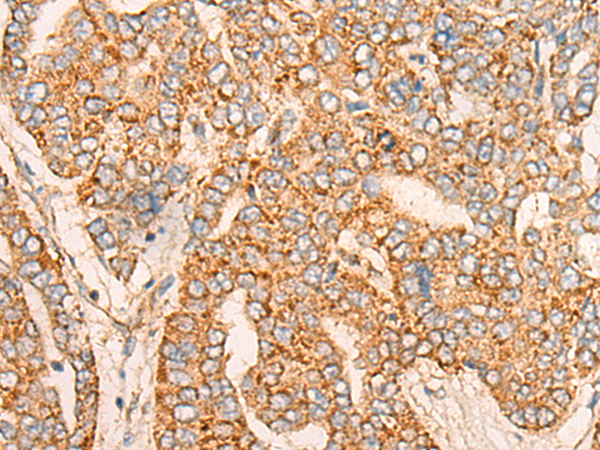

ELISA, IHC |

IHC positive control: |

Human liver cancer |

IHC Recommend dilution: |

25-100 |